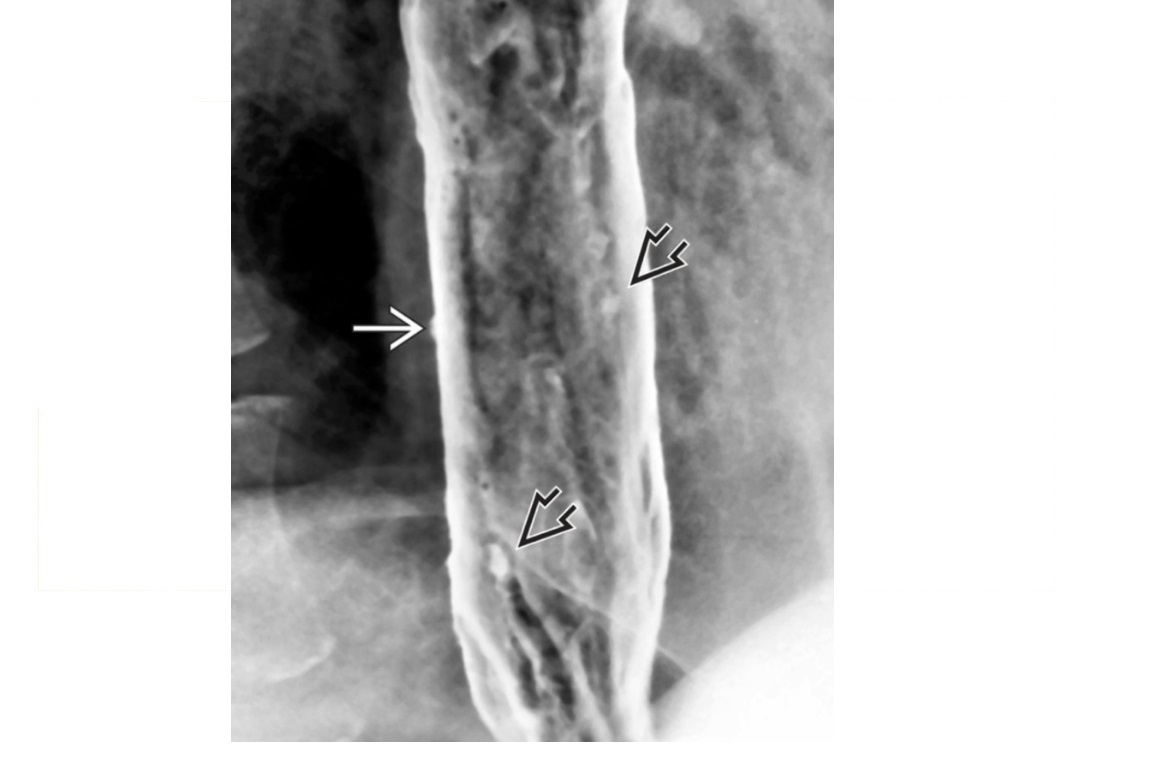

Candidiasis

irregular, longitudinal plaques with intervening normal mucosa

Typically upper 1/3 oesophagus

Immunocompromised (HIV, Transplant)

In older asymptomatic patients = Mucosal white plaques more uniform, rounded, and less well defined than candidiasis = Glycogenic Acanthosis